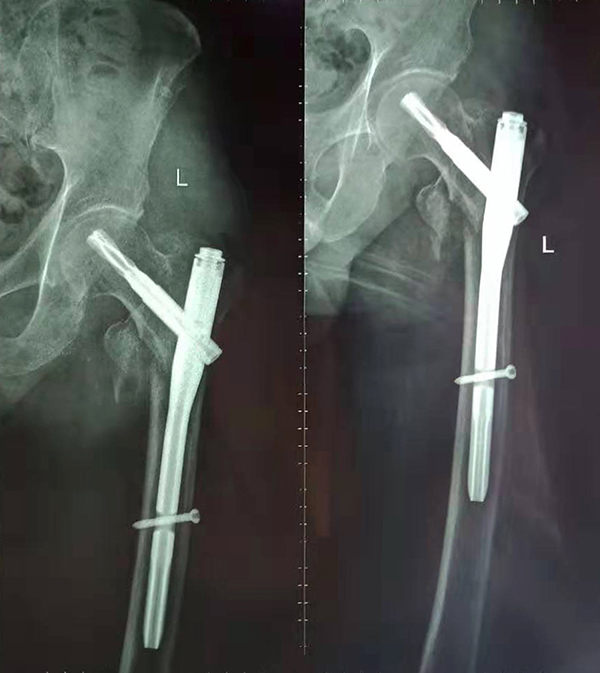

經(jīng)術(shù)前仔細的檢查和評估,與張爺爺家屬充分溝通,決定了實施閉合復(fù)位PFNA內(nèi)固定術(shù)的方案,劉鴻程主任說到,該術(shù)式的創(chuàng)傷小、出血少,適合骨質(zhì)疏松病人,術(shù)后解除患者疼痛,可以早期開始活動,便于護理。

手術(shù)后

9月10日上午,骨科順利完成張爺爺?shù)淖蠊晒谴致¢g骨折髓內(nèi)釘內(nèi)固定術(shù)。手術(shù)過程中麻醉平穩(wěn),術(shù)中出血量少,骨折手術(shù)時間持續(xù)一個多小時。